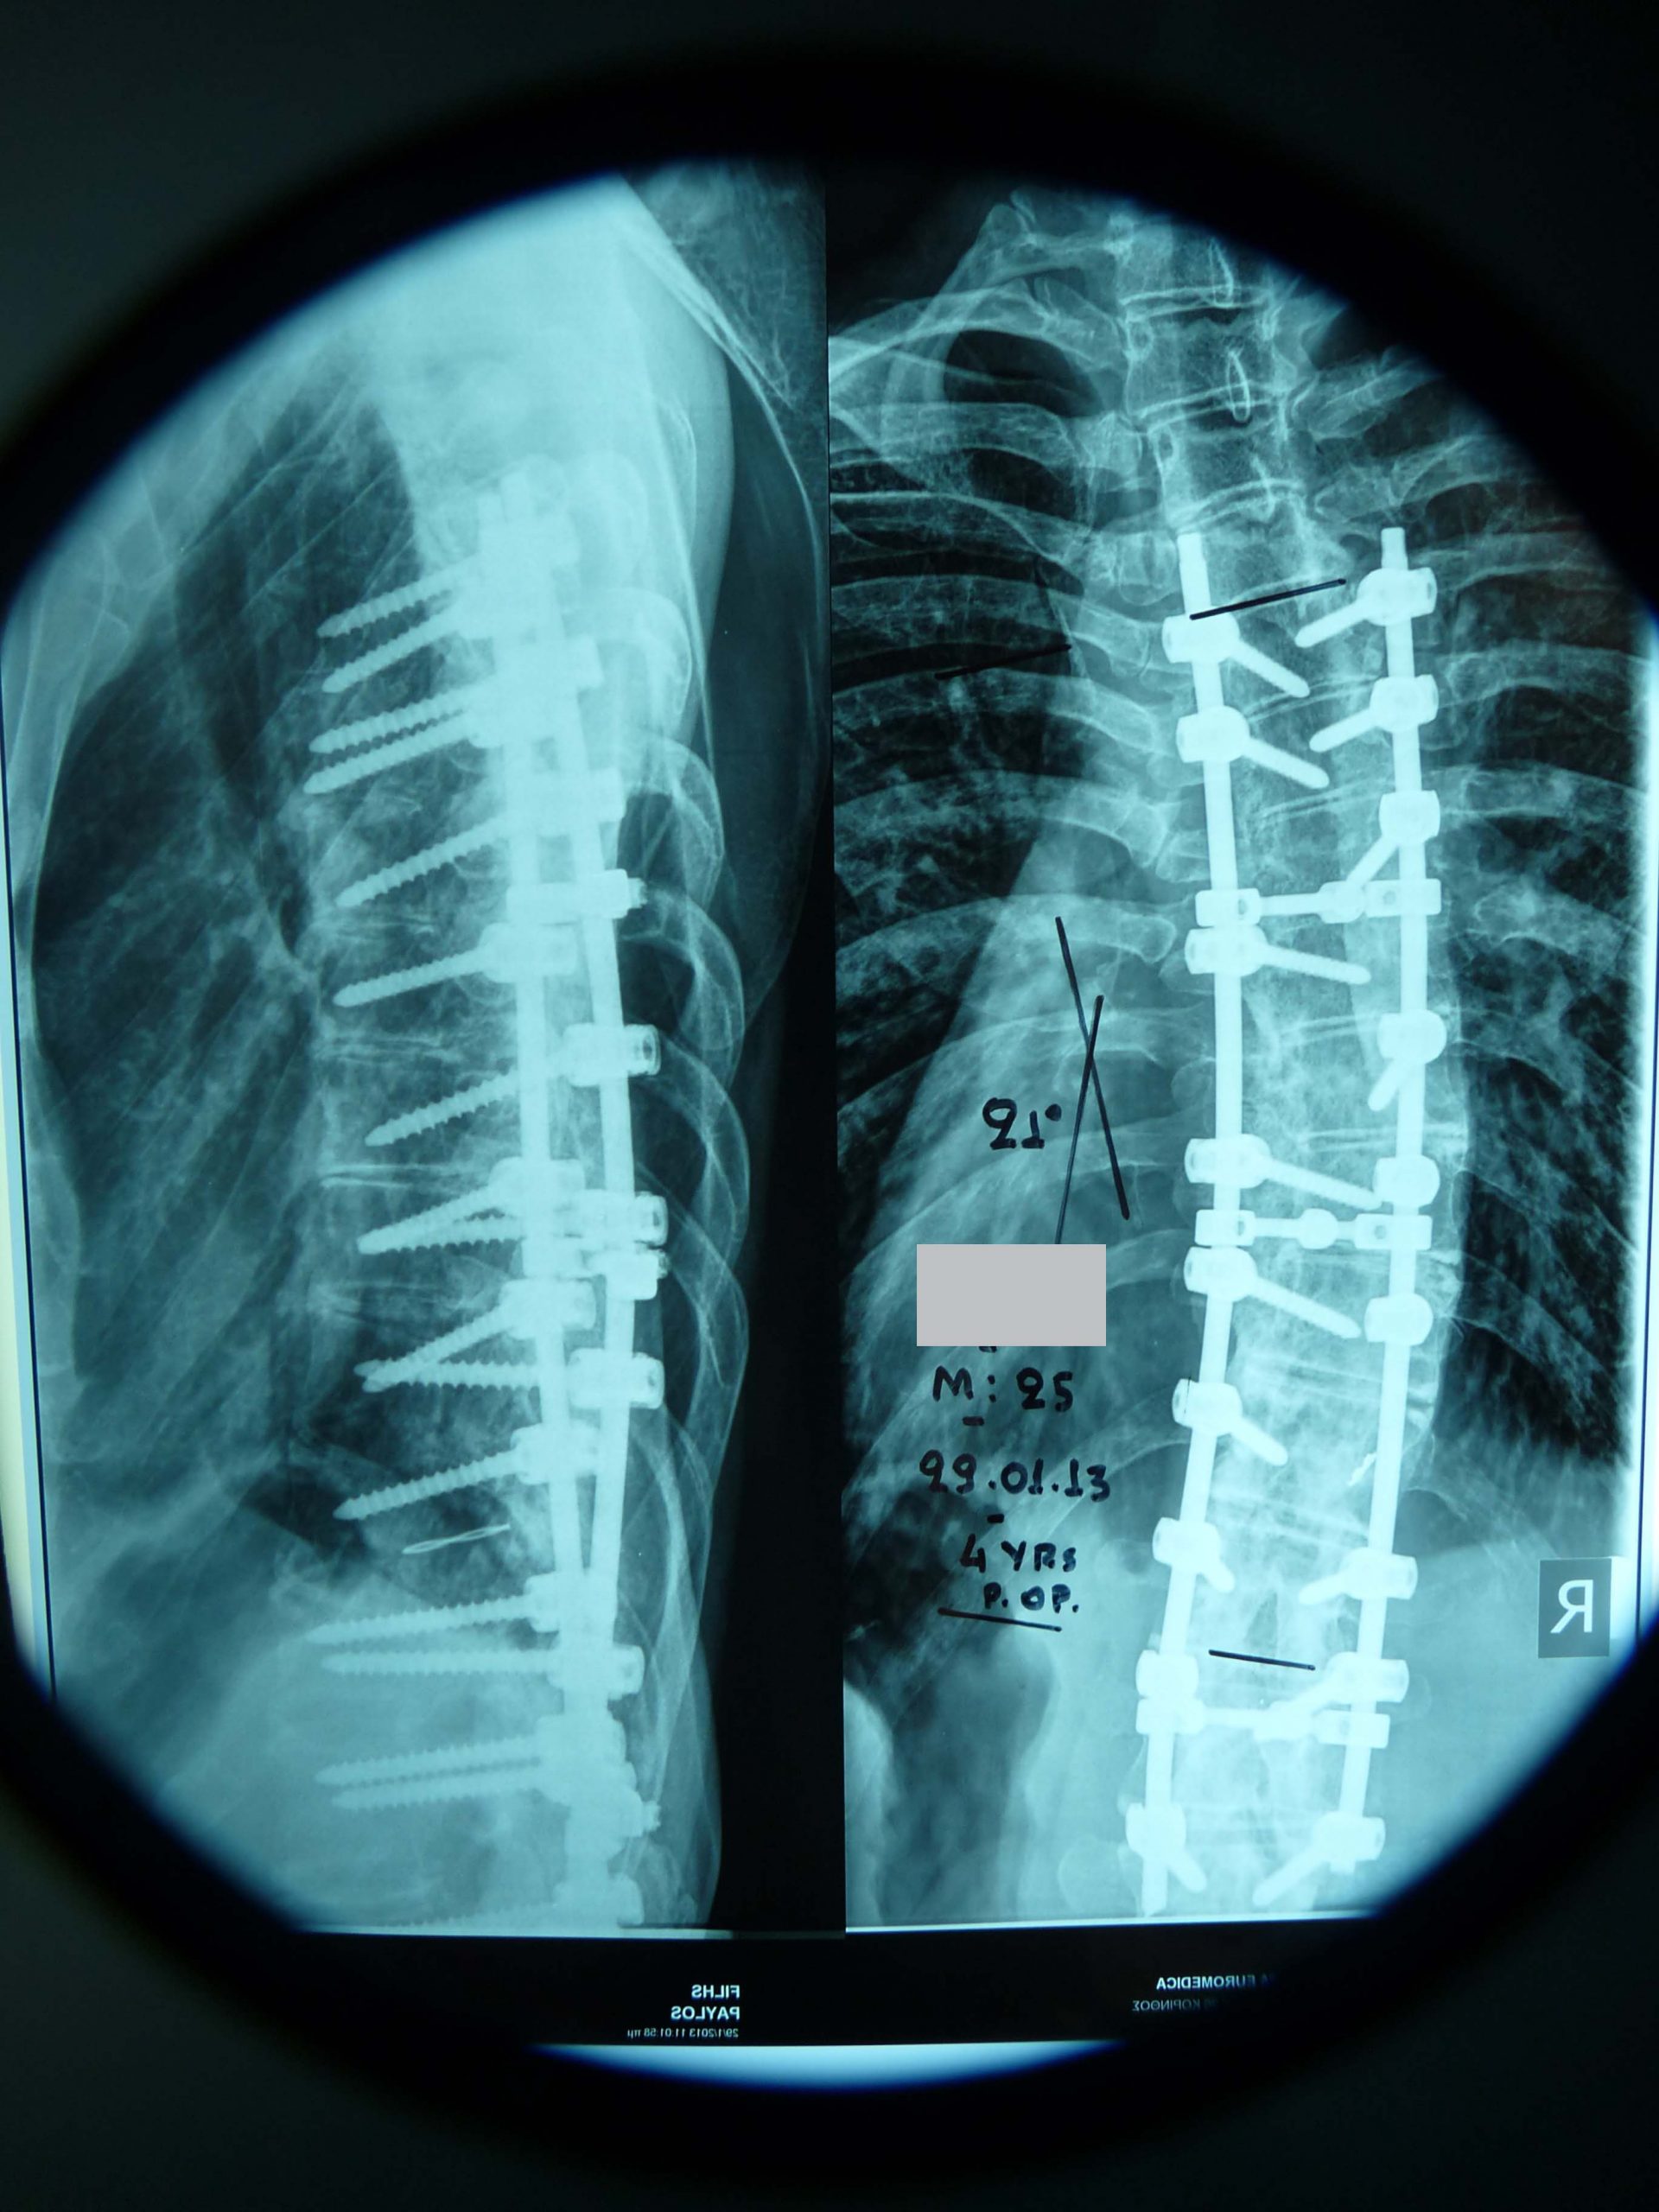

- α

- β

Εικόνα 7 (α,β) Προσθιοπισθία και πλαγία ακτινογραφία της Θωρακικής Μοίρας της Σπονδυλικής Στήλης (Θ.Μ.Σ.Σ.) πέντε χρόνια μετά τη χειρουργική επέμβαση. Διατηρείται η αρχική διόρθωση της Σπονδυλικής Στήλης.